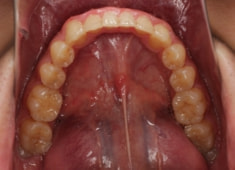

治療後(2年1ヶ月後)

歯根のパラレリングは良好です。

左上2番の歯根も問題なさそうです。

下顎8番は保定期間に入り、しばらくして咬合が安定してから抜歯する予定です。

特に左側の咬合時の顎関節の位置に改善が認められます。